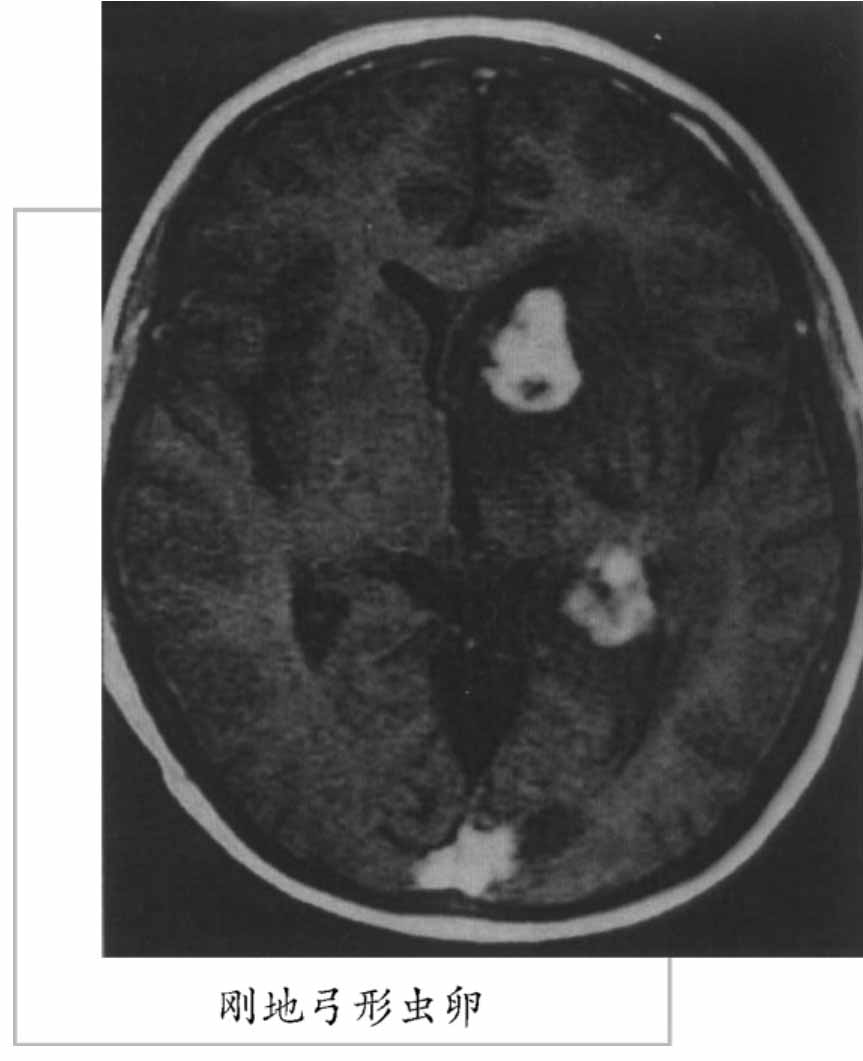

猪带绦虫

猪带绦虫属人畜共患的寄生虫。幼虫也可侵入人体。猪带绦虫的成虫寄生在人的小肠中,中间寄主为猪故得名。被寄生的猪肉通称“米猪肉”、“豆猪肉”或“珠仔肉”。人是该虫唯一的终宿主。成虫寄生于人的肠道,可引起消化不良、腹痛、腹泻或者便秘等症状。如果囊尾蚴寄生于人体,其危害性比成虫大得多,严重者导致死亡。吡喹酮、氯硝柳胺或槟榔驱虫有效。轻度感染囊尾蚴的猪肉要经无害处理后才能出售,但是肉的质量大大降低;感染严重的猪肉必须销毁。猪带绦虫成虫呈白色带状,全长为2~4米,有700~1000个节片。虫体分头节,颈部和节片3个部分。头节圆球形,直径约为1毫米,头节前端中央为顶突,顶突上有25~50个小钩,大小相间或内外两圈排列,顶突下有4个圆形的吸盘,这些都是适应寄生生活的附着器官。生活的绦虫以吸盘和小钩附着于肠黏膜上。头节之后为颈部,颈部纤细不分节片,与头节间无明显的界限,能继续不断地以横分裂方法产生节片,所以也是绦虫的生长区。节片愈靠近颈部的愈幼小,愈近后端的则愈宽大和老熟。依据节片内生殖器官的成熟情况可分为未成熟节片、成熟节片和孕卵节片或称妊娠节片3种。未成熟节片宽大于长,内部构造尚未发育。成熟节片近于方形,内有雌雄生殖器官。孕卵节片长方形,几乎全被子宫所充塞。

此外,人误食猪带绦虫虫卵,也可在肌肉、皮下、脑、眼等部位发育成囊尾蚴。其感染的方式有:经口误食被虫卵污染的食物、水及蔬菜等,或已有该虫寄生,经被污染的手传入口中,或由于肠之逆蠕动(恶心呕吐)将脱落的孕卵节片返入胃中,其情形与食入大量虫卵一样。由此可知,人不仅是猪带绦虫的终寄主也可为其中间寄主。猪带绦虫病可引起患者消化不良、腹痛、腹泻、失眠、乏力、头痛,儿童可影响发育。猪囊尾蚴如寄生在人脑的部位,可引起癫痛、阵发性昏迷、呕吐、循环与呼吸紊乱;寄生在肌肉与皮下组织,可出现局部肌肉酸痛或麻木;寄生在眼的任何部位可引起视力障碍,甚至失明。此虫为世界性分布,但感染率不高,我国也有分布。